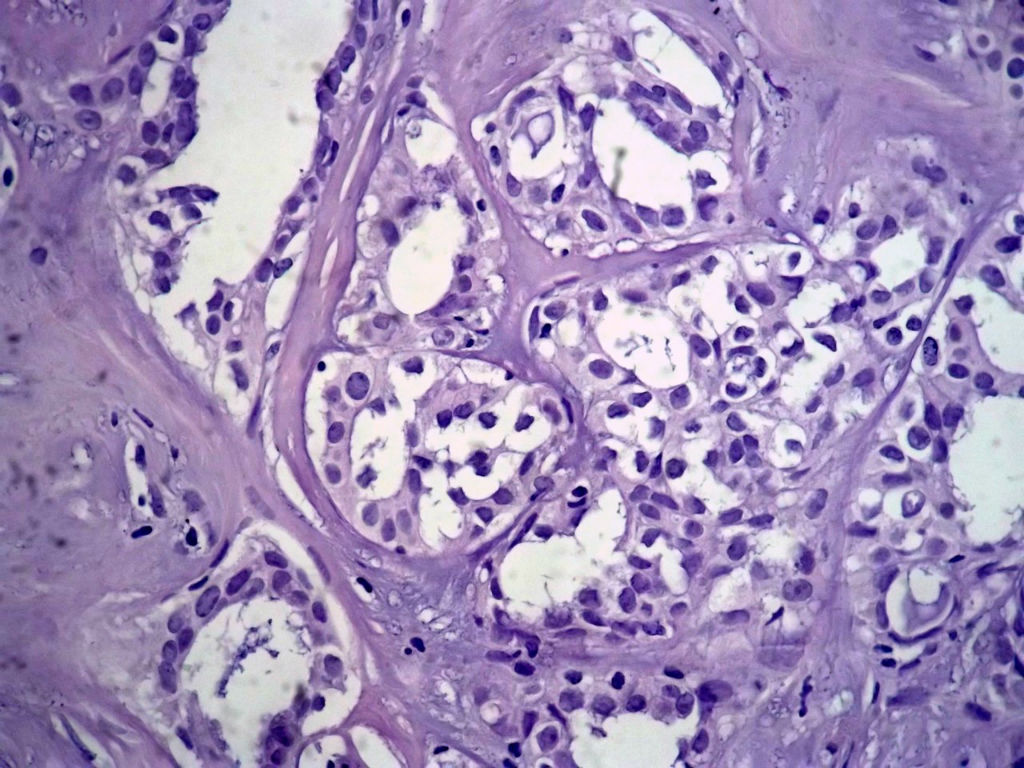

本例太完美了,也非常惊险,真的,至少在我们中国的这个病理环境下能做到这样真心不错。这是个罕见病例,居然冰冻让你碰上了,从冰冻——常规——IHC都完备。我从冰冻看到常规未看免疫组化之前还一直犹豫是不是癌?是癌但一定是您说的分泌性癌吗?看常规时只是觉得浸润性癌够了,后来看到常规的筛状结构+分泌物才确定形态学也够了,就差IHC了,结果您贴出来上级医院的IHC结果真的是3阴,S-100+,高分子量CK部分+,这个表达模式完全符合分泌性癌(我也遇到一个分泌性癌,IHC表达方式完全和您的这例一样),当然必须是结合形态学了。

Secretory breast carcinomas (o0.15% of breast tumors) are associated with a characteristic morphology and a

favorable prognosis. Remarkably, this entity is the only epithelial tumor of the breast with a balanced

translocation, t(12;15), that creates an ETV6-NTRK3 gene fusion encoding chimeric tyrosine kinase also

encountered in cellular mesoblastic nephroma and infantile fibrosarcoma. The aim of this study was to

determine the phenotypic class (ie luminal A/B, ERBB2, basal-like) of secretory breast carcinoma. A series of six

secretory breast carcinomas were identified in our files. The ETV6 rearrangement was confirmed in all cases by

fluorescence in situ hybridization. Immunophenotype was assessed with anti-ER, PR, ERBB2, KIT, EGFR,

E-cadherin, vimentin, PS100, smooth muscle actin, basal (CK5/6 and 14), luminal cytokeratins (CK8/18) and p63

antibodies. In situ and invasive components shared the same immunoprofile and were ER, PR, ERBB2 negative

with expression of basal cytokeratins. ETV6 gene alterations were present in both in situ and invasive

components, highlighting their genetic similarities. The immunoprofile data (triple-negative with expression of

basal markers) showed that secretory breast carcinomas with ETV6-NTRK3 fusion gene belong to the

phenotypic basal-like spectrum of breast carcinomas. These results support the hypothesis that secretory

breast carcinomas have immunohistochemical and genetic features that distinguish them from other basal-like

tumors of the breast.